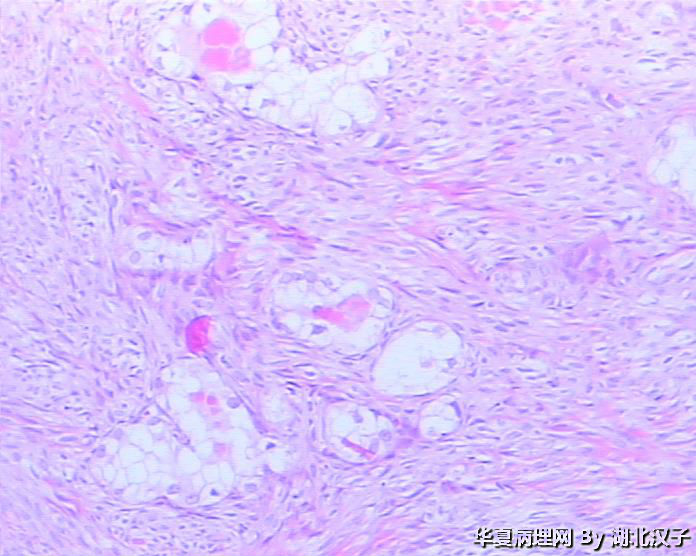

宫颈肿物,46岁,发现6月

宫颈管息肉

腺纤维瘤

良性病变,宫颈小囊肿,